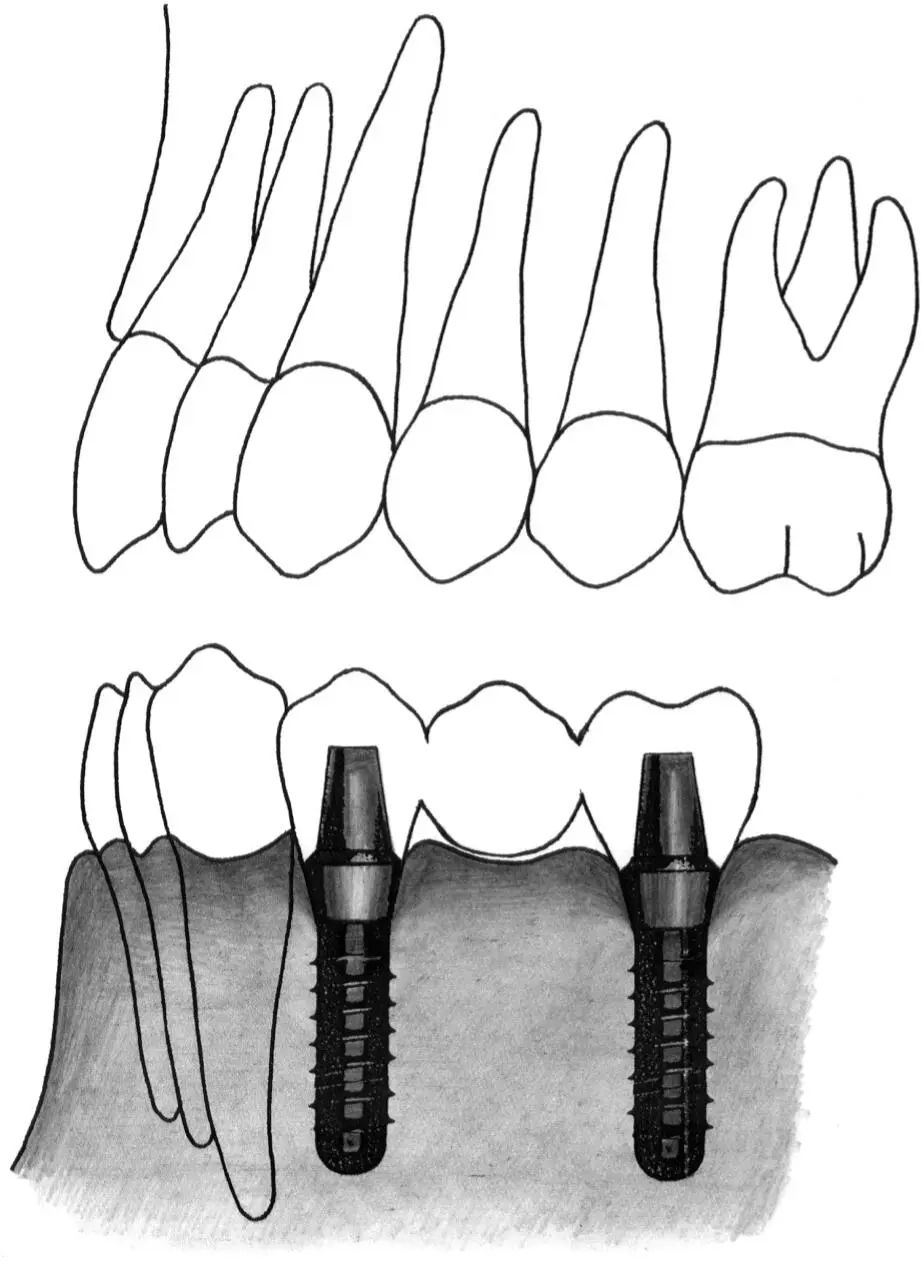

Figs 1-11g and 1-11h Occlusal (g) and lateral (h) views of regular neck and wide neck implants. When a regular neck implant and a wide neck implant are indicated to replace a missing second premolar and molar, the regular neck implant should be placed 4 to 5 mm from the tooth and the wide neck implant placed approximately 9 mm from the anterior implant.